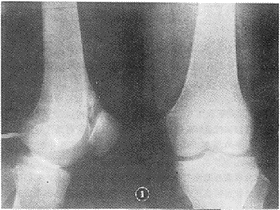

2.1 X线表现:患病关节间隙或关节周围如滑囊与腱鞘滑囊内见一枚或多枚游离体,大小不一,形态从绿豆大至长条形,甚至似“钟乳石”样(图1),部分呈椭圆形,最大3 cm×1.5 cm×1.5 cm(图2)。游离体钙化与骨化常不均匀或呈环状或呈点、斑点样改变,多位于游离体外围。游离体中心为一密度减低区。1例CT见游离体位于关节囊内呈沙粒样改变(图3)。除上述外,患病关节间隙变窄,关节骨面吸收,而致增生肥大3例(图4),关节囊肿胀4例,其余关节骨与关节间隙均正常。

滑膜骨软骨瘤病病因至今不明,能引起滑膜化生原因多种多样,如胚胎、外伤、炎变与肿瘤等。认同胚胎、外伤学说者多。病名曾相当混杂,如滑膜软骨瘤病、滑膜骨软骨瘤、腱鞘滑膜(骨)软骨瘤病或滑膜良性肿瘤等。现多数学者主张[1]命名为滑膜骨软骨瘤病。分原发性与继发性两大类。原发性中病因以胚胎学说为主。既残存胚胎组织活化、增生形成,引起滑膜化生。病史相对较长。原发性中按部位又分原发于关节腔、滑囊与腱鞘滑膜,前二者与关节交通,后者不与关节交通。继发性[1]是指关节已存在某些骨关节病,因软骨或骨性关节面碎裂、刺激关节滑膜化生、引起关节内游离体形成。继发性中病因以外伤、炎变学说为主。本组病例中属原发性6例,继发性4例。其中原发性中游离体多偏大,且数目多,游离体除位于关节腔外,还位于滑囊与腱鞘滑囊。如本组中右肩关节三角肌滑囊区域见多个呈“钟乳石”样游离体。原发性中除游离体外,往往关节骨受累不明显。继发性中游离体少,且体积小,甚至呈沙粒样改变,游离体常位于关节腔内,关节骨受累明显,如关节肿胀,关节骨退行性变,关节间隙变窄等,往往诊断中易误诊。本组3例均误诊。继发性病例中病史相对较短,症状重,如关节绞锁、活动受限等。滑膜骨软骨瘤病属自愈性疾病,实际病例多于临床所见。本病病理分期[2]为三期,Ⅰ期滑膜内病变期,Ⅱ期游离体形成期,Ⅲ期继发关节退变期。本组1例X线未诊断,关节镜病理证实属Ⅰ期改变。